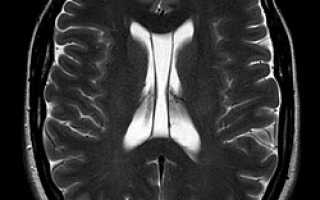

Полость прозрачной перегородки на МРТ головного мозга

1. Первичные — доброкачественные бессимптомные образования, появившиеся на ранних сроках формирования плода, рассасывающиеся самостоятельно, диагностируются у 60% новорожденных. Если женщина не доносила малыша, вероятность аномалии — 100%. Магнитно-резонансная томография «видит» новообразование с четкими гранями, однотипным содержимым;

Подобное заболевание в результате прохождения МРТ обнаруживается у четвертой части пациентов.

• магнитно-резонансную томографию головного мозга;

МРТ, КТ дифференцируют кисту от злокачественного образования. Рентгеноконтрастное средство, введенное в вену, реагирует на опухоль.

Чтобы новообразование не выросло до больших размеров, пациенту с патологией важно вовремя диагностировать заболевание, регулярно делая МРТ, КТ.